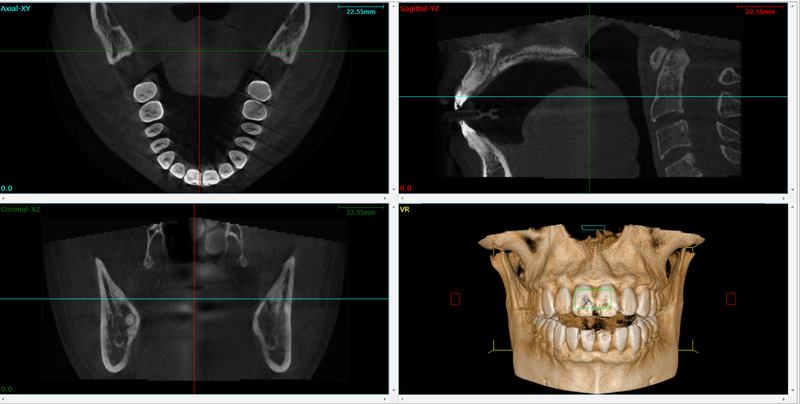

تصویربرداری سه بعدی در حوزه فک و صورت به مجموعه تکنولوژی هایی گفته می شود که امکان مشاهده ساختار های استخوانی، دندانی و در بعضی موارد بافت نرم را به صورت حجمی و سه بعدی فراهم می کنند. برخلاف رادیوگرافی های معمولی که یک تصویر تخت و دو بعدی از فک ارائه می دهند، در روش های سه بعدی می توان ساختار ها را از زوایای مختلف چرخاند، برش های سطحی و عمقی ایجاد کرد و اندازه گیری های بسیار دقیق تری انجام داد. مهم ترین فناوری سه بعدی در دندانپزشکی و جراحی فک، سی بی سی تی است که مخفف Cone Beam Computed Tomography می باشد. این روش با استفاده از یک پرتو مخروطی شکل اشعه ایکس، حجم کاملی از فک و صورت را اسکن و سپس با نرم افزار، مدل سه بعدی بازسازی می کند. برای جراح فک و صورت، این مدل مثل یک نقشه دقیق است که قبل از عمل، تمام جزئیات را نشان می دهد.

در حوزه فک و صورت، چند نوع اصلی فناوری برای تصویربرداری سه بعدی وجود دارد که هر کدام کاربرد و ویژگی های خاص خود را دارند. رایج ترین و شناخته شده ترین روش، سی بی سی تی است که به طور گسترده در مطب های دندانپزشکی و کلینیک های جراحی فک و صورت استفاده می شود. سی بی سی تی نسبت به سی تی اسکن پزشکی، دوز اشعه کمتری دارد، دستگاه آن کوچک تر و مناسب مطب است و برای بررسی ساختار های استخوانی و دندان ها دقت بالایی ارائه می دهد. این روش برای برنامه ریزی جراحی فک، ایمپلنت، کشیدن دندان های نهفته، بررسی مفصل فکی گیجگاهی، ضایعات استخوانی و ارزیابی راه هوایی بسیار مفید است. نوع دیگر، سی تی اسکن پزشکی معمولی است که در بیمارستان ها استفاده می شود و برای موارد پیچیده تر، تروما های شدید و بررسی همزمان بافت نرم و استخوان کاربرد دارد.

ناهنجاری های اسکلتی فک مانند جلو بودن بیش از حد فک پایین، عقب بودن فک بالا، انحراف چانه به یک سمت، رشد ناکافی یا بیش از حد فک ها و مشکلات ترکیبی فک و صورت، معمولا با معاینه ظاهری و سفالومتری دو بعدی تا حدی قابل تشخیص هستند. اما برای تصمیم گیری دقیق در مورد نوع و میزان جراحی، تصویربرداری سه بعدی نقش کلیدی دارد. سی بی سی تی به جراح اجازه می دهد طول، عرض و ارتفاع فک ها را در سه بعد اندازه گیری کند، عدم تقارن ها را به صورت عددی و قابل مقایسه ببیند و رابطه فک ها با راه هوایی، سینوس ها و مفاصل را ارزیابی کند. مثلا در بیماری که احتمال انسداد راه هوایی و آپنه خواب دارد، می توان ضخامت و حجم راه هوایی خلف زبان و پشت کام نرم را در مدل سه بعدی بررسی کرد و تاثیر جراحی فک بر بهبود یا بدتر شدن آن را پیش بینی کرد.

همچنین تصویربرداری سه بعدی به تشخیص ضایعات پنهان در استخوان فک کمک می کند؛ ضایعاتی مانند کیست ها، تومور ها، نواحی جذب استخوان، شکستگی های قدیمی یا جوش نخورده و تغییرات مفصل فکی گیجگاهی که ممکن است در تصاویر دو بعدی به راحتی دیده نشوند. این اطلاعات برای برنامه ریزی جراحی بسیار حیاتی است، زیرا وجود یک ضایعه پنهان در مسیر برش جراحی یا نزدیک ریشه دندان ها می تواند ریسک آسیب حین عمل را بالا ببرد. در کودکان و نوجوانان که هنوز رشد فک کامل نشده، تصویربرداری سه بعدی به پزشک کمک می کند وضعیت صفحات رشد، رویش دندان های دائمی و رابطه آنها با فک را بهتر درک کند و بین درمان ارتودنسی و جراحی فک بهترین زمان بندی را انتخاب کند.

بسیاری از بیمارانی که نیاز به جراحی فک دارند، همزمان به درمان های دیگر مانند ایمپلنت های دندانی، پیوند استخوان در فک بالا یا پایین، کشیدن دندان های نهفته و اصلاح نقص های استخوانی نیز احتیاج دارند. تصویربرداری سه بعدی در همه این موارد نقش مهمی ایفا می کند. در ایمپلنت، سی بی سی تی امکان اندازه گیری دقیق ارتفاع، عرض و زاویه استخوان را فراهم می کند و محل دقیق عصب تحتانی، سینوس فکی و ساختار های حساس دیگر را نشان می دهد. با استفاده از این اطلاعات، می توان محل و زاویه ایمپلنت ها را به صورت مجازی طراحی کرد و گاید جراحی ایمپلنت ساخت که دقت قرار دادن فیکسچر را بسیار بالا می برد و ریسک آسیب عصب یا سوراخ شدن سینوس را کاهش می دهد. همچنین در پیوند استخوان برای افزایش ارتفاع سینوس یا بازسازی نقص های استخوانی، حجم کمبود استخوان و محل مناسب برداشت و قرار دادن گرافت با کمک سی بی سی تی به خوبی مشخص می شود.

در مورد دندان های نهفته مانند دندان عقل نهفته یا نیش نهفته، تصویربرداری سه بعدی به طور دقیق موقعیت دندان نسبت به ریشه های مجاور و عصب ها را مشخص می کند. این موضوع برای کاهش خطر آسیب به عصب و ریشه های سالم حین جراحی بسیار مهم است. علاوه بر این، در ضایعات پاتولوژیک مانند کیست ها و تومور ها، تصویربرداری سه بعدی مرز ضایعه، عمق درگیری استخوان و ارتباط با ساختار های مهم را نشان می دهد و به جراح کمک می کند نوع و وسعت جراحی را بهتر برنامه ریزی کند. ترکیب داده های سه بعدی با چاپ سه بعدی امکان ساخت مدل های فیزیکی از فک بیمار را نیز فراهم کرده است که برای تمرین قبل از عمل، آموزش دانشجویان و توضیح طرح درمان به بیمار بسیار کاربردی است. همه این موارد نشان می دهد که نقش تصویربرداری سه بعدی فقط محدود به خود جراحی فک نیست، بلکه در تمام اقدامات همراه و تکمیلی نیز اهمیت دارد.